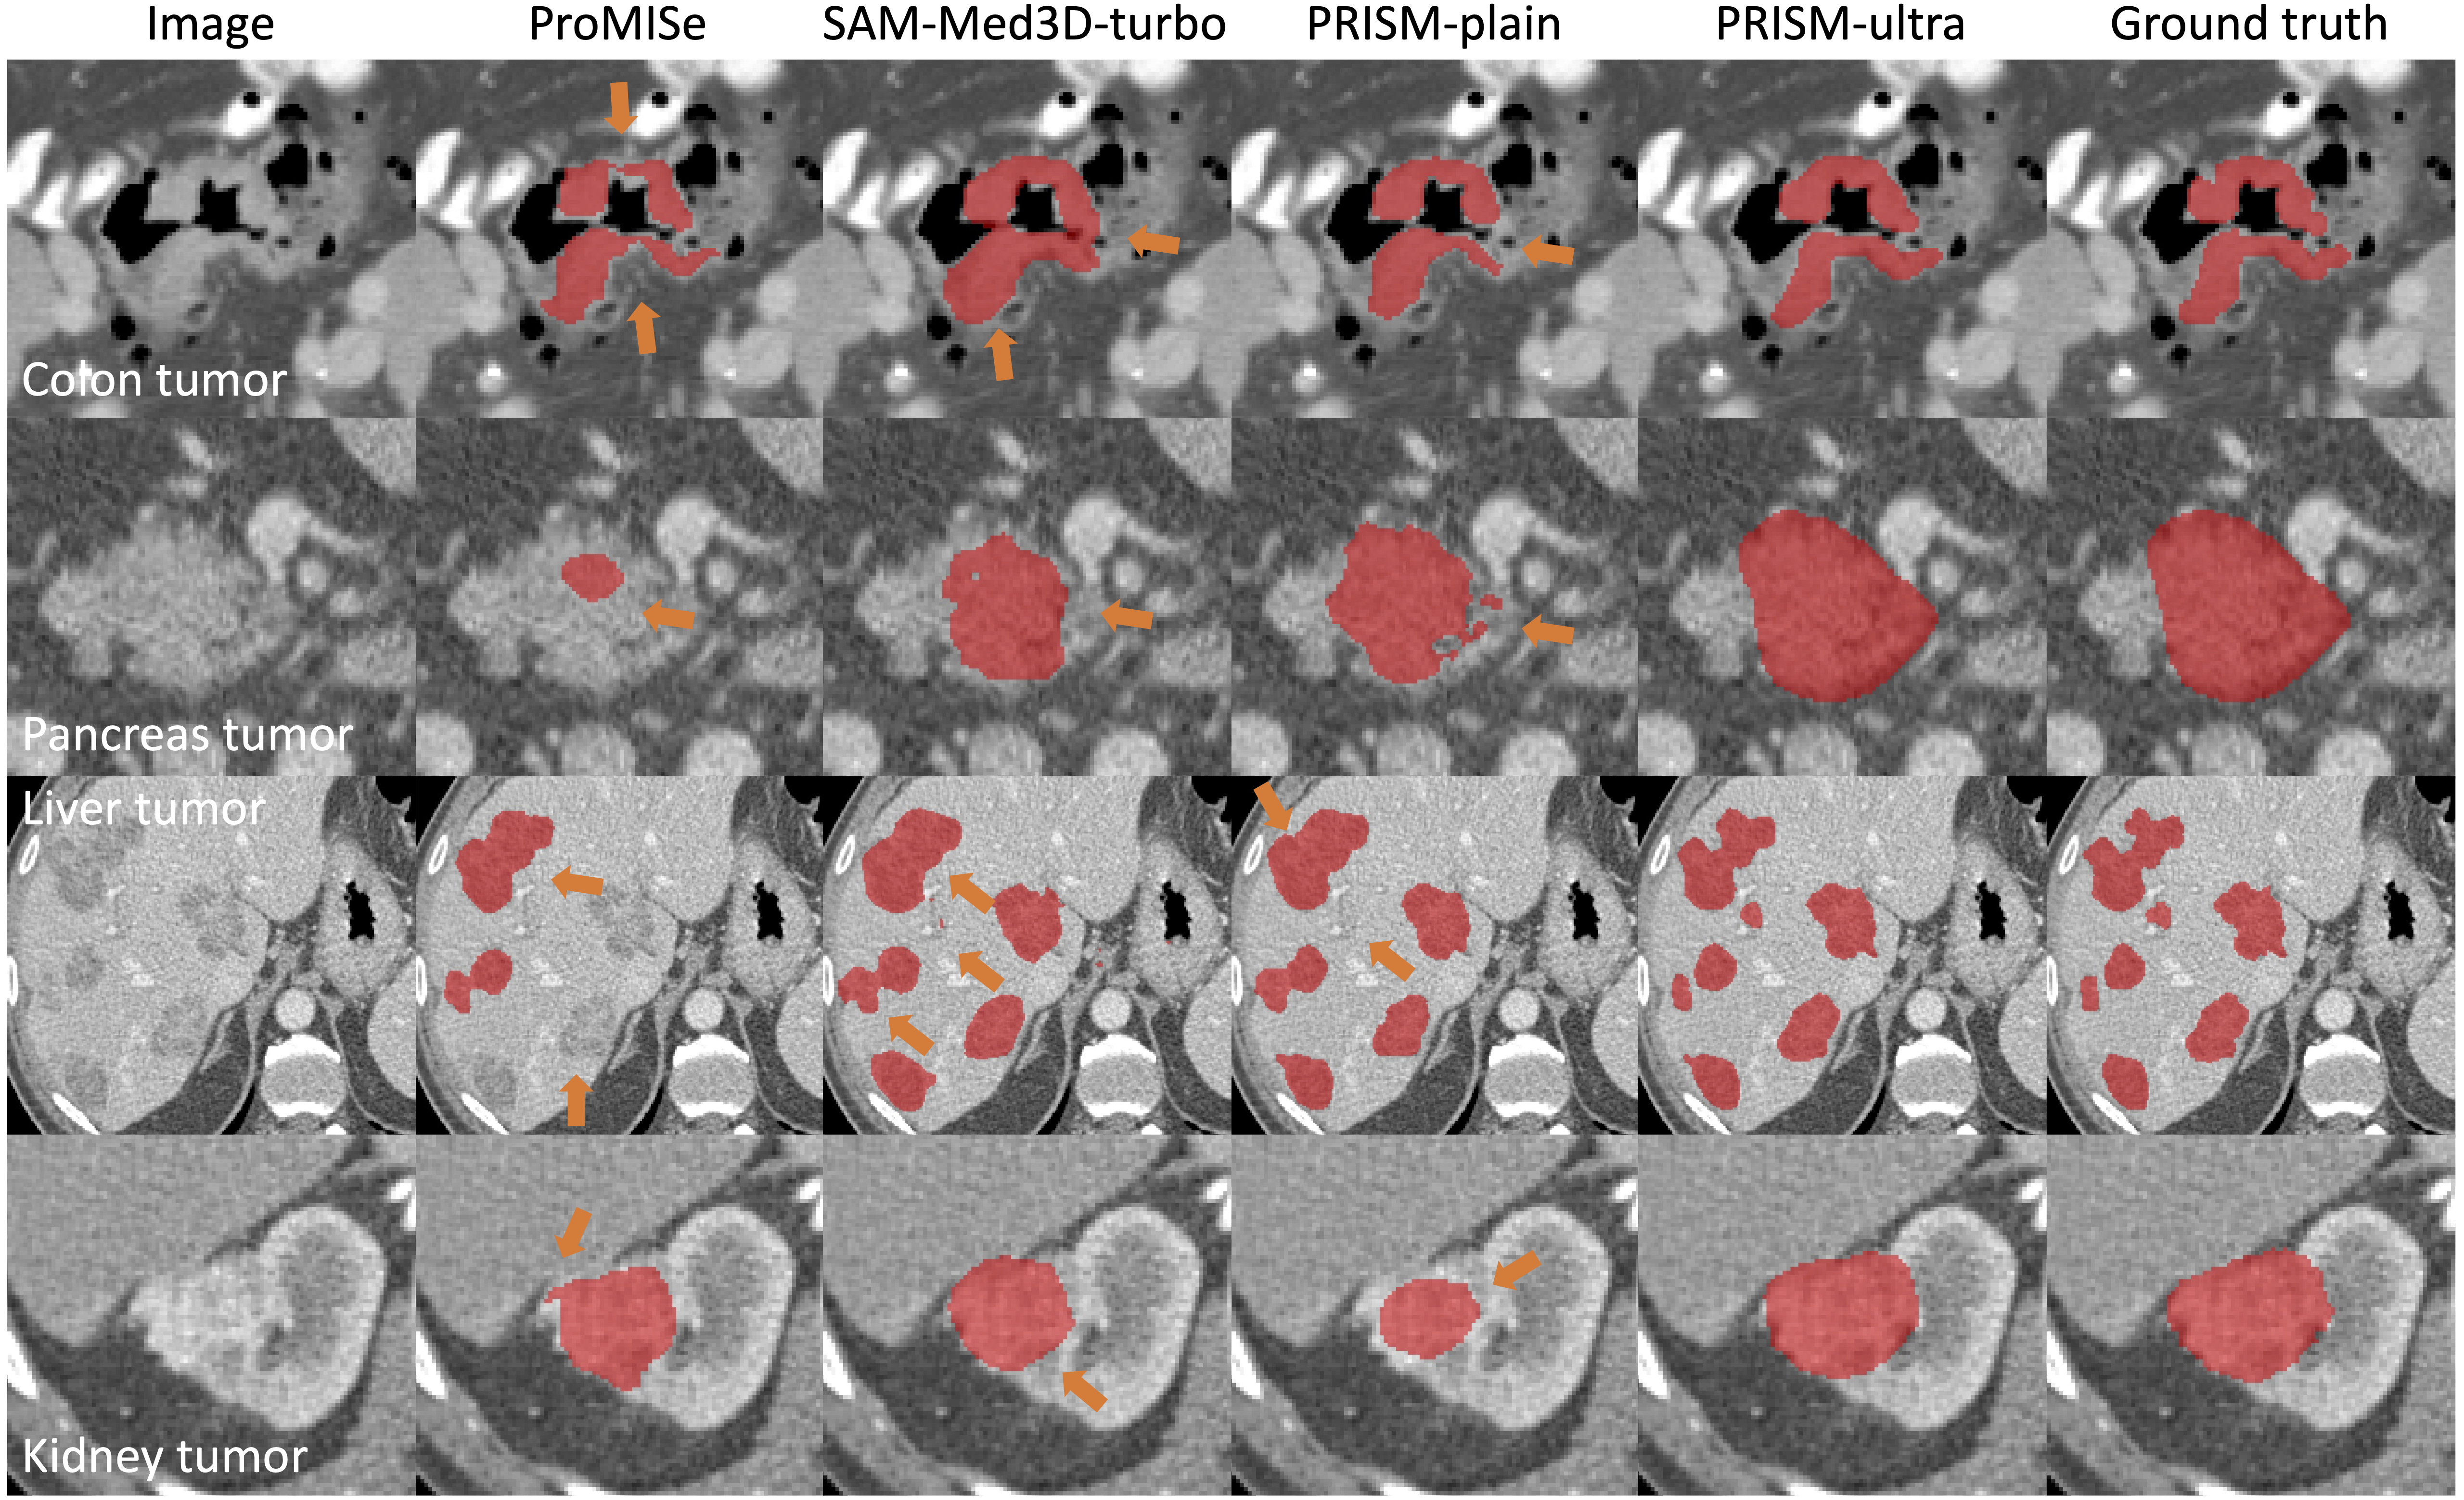

PRISM tumor segmentation examples

Briefly, PRISM produces tumor segmentation with mean Dice values of 93.79 (colon), 94.48 (pancreas), 94.18 (liver), and 96.58 (kidney).

| Qualitative results with compared methods | ![]() |

We used four public datasets for 3D tumor segmentation in colon, pancreas, liver and kidney.